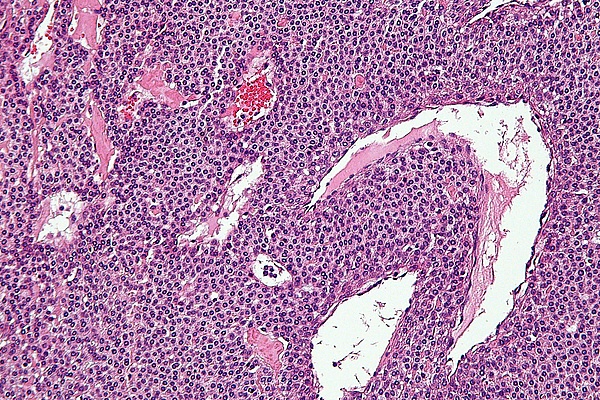

Наиболее адекватным считается термин параганглиома, так как он соответствует понятию о гистологическом строении данной опухоли и подразумевает общность патогенеза с гомологичными новообразованиями другой локализации, так же развивающихся из параганглионарной ткани — параганглиомами лёгких, кожи, надпочечников (феохромоцитома). Параганглиомы латерального основания черепа ассоциированы с парасимпатическими ганглиями в обилии представленными в этой анатомической зоне.

Гломусные опухоли составляют 0,6 % всех новообразований головы и, как правило, носят спорадический характер, впрочем, вероятность генетической предрасположенности параганглиом достигает 30 % у членов семьи заболевшего. Частота встречаемости гломусной опухоли уха составляет 1:300000. В некоторых случаях она секреторно активна — и продуцирует ряд высокоактивных веществ, таких как допамин и норадреналин. В редких случаях (до 5 %) гломусная опухоль приобретает злокачественное течение. Распределение по полу отчётливо показывает, что женщины болеют чаще мужчин — 3:1, а дебют заболевания обычно выпадает на пятую и шестую декады жизни. Гломусная опухоль является наиболее часто встречающейся опухолью среднего уха и находится на втором месте среди опухолей височной кости после шванномы вестибулокохлеарного нерва.